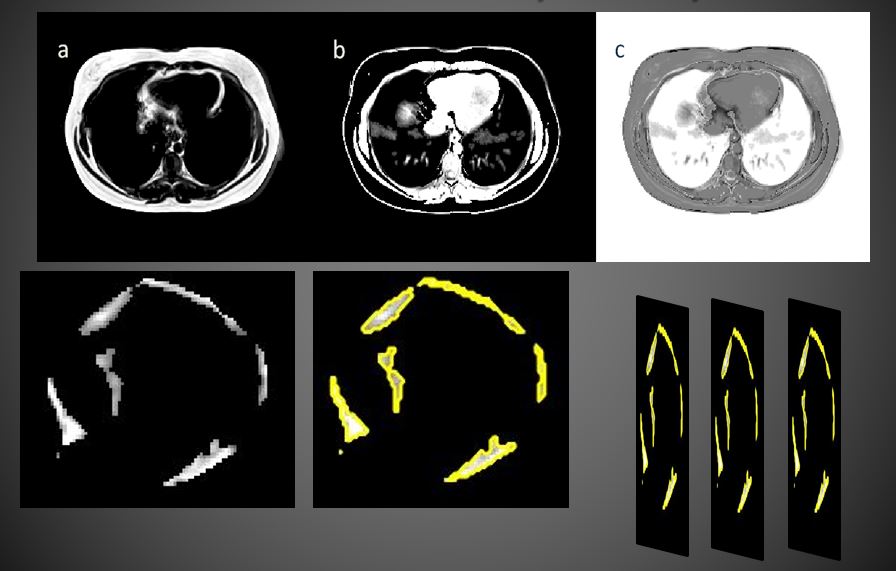

1) 3D Segmentation of Epicardial Adipose Tissue

from Cardiac MRI

Obesity is a wide-ranging health problem and fat

depots around the heart have been linked to the risk

of cardiovascular disease. Magnetic Resonance

Imaging (MRI) has emerged as the standard for

quantifying epicardial fat for clinical studies but

requires the analysis of a large number of images in a

short time. We work on 3D segmentation of

epicardial adipose tissue (EAT) and the development of

tools to aid in studies of EAT and its relationship to

cardiovascular disease and risk.